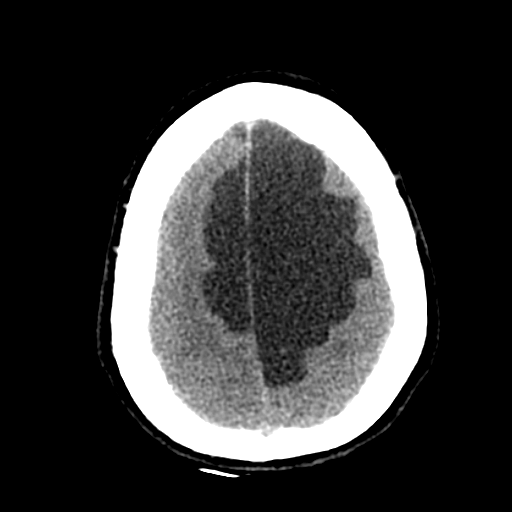

Больному около 55 лет, клинику дает не сколько само образование, а компрессия структур мозга, базально вообще беда (отчасти видно компреммию некоторых базальных цистерн мозга). Сразу скажу насчет эпидермоидной кисты - ДВИ не будет :)

Однозначно киста, значит, осталось выяснить какая, холестеатома или арахноидальная?

Сравните очертания кист в первом и последнем наблюдениях...